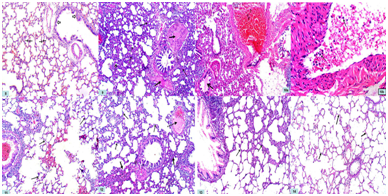

Lung

The hematoxylin& eosin - stained sections of control lung specimens showed normal-appearing lung architecture with expanded alveoli separated by thin interalveolar septa and members of the bronchial tree in between (Fig. 8). Lung specimens from the AP group demonstrated thickened interalveolar septa and dilated congested blood vessels with acidophilic hyaline exudate. There was also acidophilic material in the bronchiolar lumen. Inflammatory cellular infilteration in addition to collapsed alveoli were observed (Figures 9&10a,&10b).

Regarding lung sections of bee venom pretreated rats (BVL group), they showed normal expanded alveoli with thin interalveolar septa with intrabronchiolar congestion (Figure 11). Bee propolis pretreated rats (BPL group), they showed areas of expanded alveoli with thin interalveolar septa. Other areas showed thickened interalveolar septa in addition to presence of dilated congested blood vessels with acidophilic hyaline exudate (Figure 12). Combined therapy treated rats (CT group) revealed marked improvement with expanded alveoli and thinning of interalveolar septa. Disappearance of congestion and inflammatory cellular infiltration was observed (Figure 13).

In bee venom only treated rats (BV group), they appeared normal compared to the control group (Figure 14). No remarkable difference was observed in propolis only treated rats (BP group) compared with group VI.

Figure 8 A photomicrograph of a section of a rat lung in group I (CG) showing normal-appearing lung architecture with the expanded alveoli separated by thin interalveolar septa (thin arrows) and members of the bronchial tree in between (thick arrows). Hx. &E; x 100

Figure 9 A photomicrograph of a section of a rat lung in group II (AP group) showing thickened interalveolar septa (thin arrows) and acidophilic hyaline exudate in the blood vessels (thick arrows). Collapsed alveoli are observed (dotted arrows). Hx. &E; x 100

Figures 10a&b Photomicrograph of a section of a rat lung in group II (AP group) showing mononuclear inflammatory cellular infiltrate (thin arrows) inside dilated and congested (C) blood vessels. There is also acidophilic material in bronchiolar lumen (thick arrows). a- Hx. &E; x 100 b- Hx. &E; x 400

Figure 11 A photomicrograph of a section of a rat lung in group III (BVL group) showing normal expanded alveoli with thin interalveolar septa (arrows) with intrabronchiolar congestion (C). Hx. &E; x 100

Figure 12 A photomicrograph of a section of a rat lung in group IV (BPL group) showing areas of expanded alveoli with thin interalveolar septa (thin arrows). Other areas showed thickened interalveolar septa (thick arrows) in addition to presence of dilated congested blood vessels with acidophilic hyaline exudate (dotted arrow). Hx. &E; x 100

Figure 13 A photomicrograph of a section of a rat lung in group V (CT group) showing marked improvement with expanded alveoli and thinning of interalveolar septa (arrows). Disappearance of congestion and inflammatory cellular infiltration is observed. Hx. &E; x 100

Figure 14 A photomicrograph of a section of a rat lung in groups VI (BV group) showing normal appearance of alveoli and interalveolar septa (arrows) comparable with the control group. Hx. &E; x 100